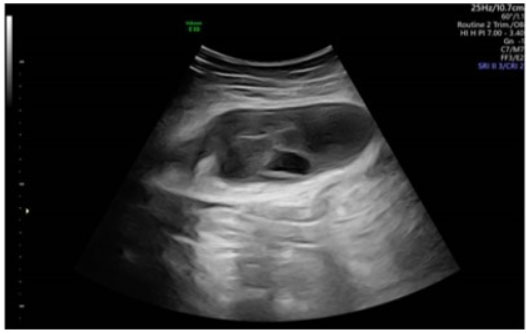

Figure 4: Three months postoperative rectus sheath hematoma on US. Further reduction in the size of the hematoma. The hematoma appears more condensed and hyperechoic, with signs of connective tissue formation, a more solidified mass-like state.